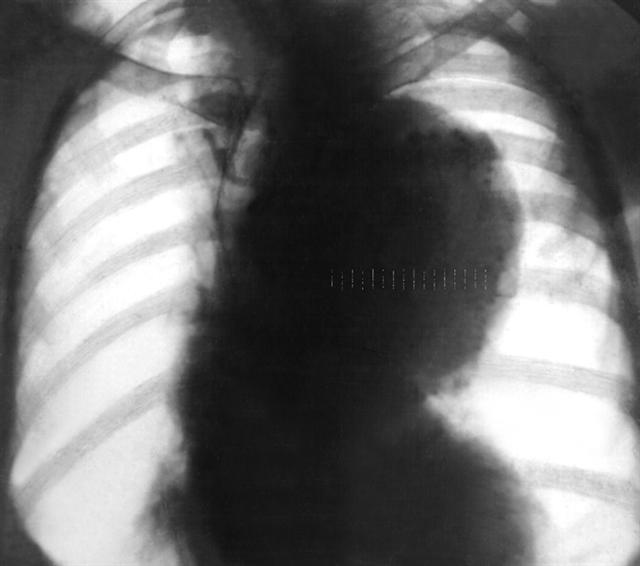

Рис. 1. Рентгенограмма грудной клетки при мешковидной аневризме грудной части аорты (прямая проекция): резкое расширение дуги аорты полуовальной формы с ровными контурами.